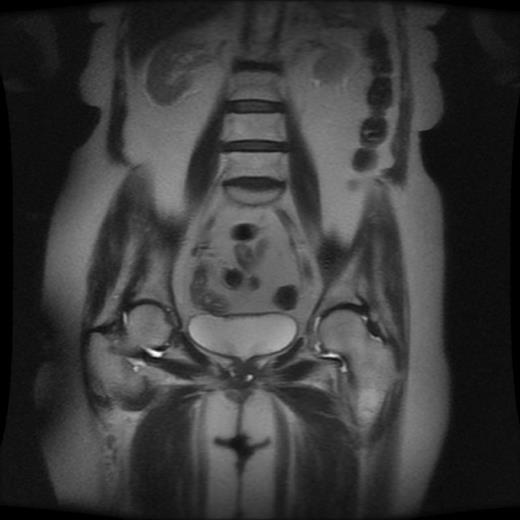

An 81 year old female complained of suprapubic pain, urethral discharge, urinary frequency, urgency, and stranguria. Past medical history included vulvectomy for vulvar carcinoma, non-Hodgkin’s lymphoma in remission after cyclophosphamide, and a 40 pack per year history of tobacco use. Physical examination revealed a firm tender mass at 7 o’clock in the urethra. Magnetic resonance imaging (MRI) revealed fluid filled lesions on either side of the urethra, see Figure 1. Flexible cystoscopy was negative.

Historically, double balloon positive pressure urethrography and voiding cystourethrogram were the diagnostic studies of choice. However, these techniques are invasive and will miss non-communicating diverticula (1). MRI permits noninvasive imaging of diverticula independent of voiding and free of ionizing radiation while allowing for assessment of the extent, structure, and complexity of the diverticulum. With MRI, simply identifying a diverticulum adjacent to the urethra is all that necessary for diagnosis regardless of presence of a diverticular neck (2).